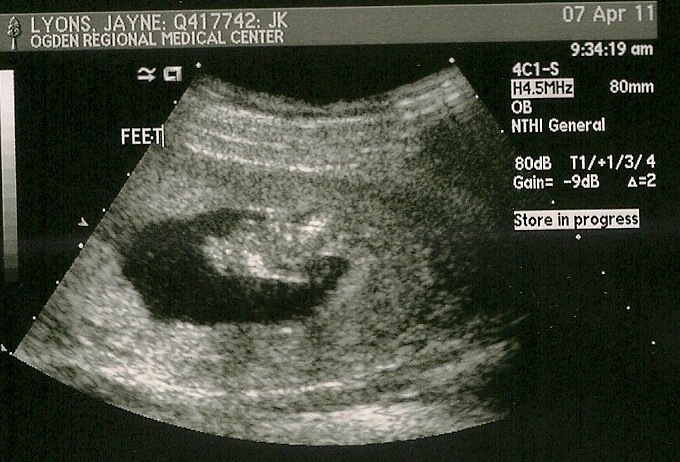

Her little feetsies!